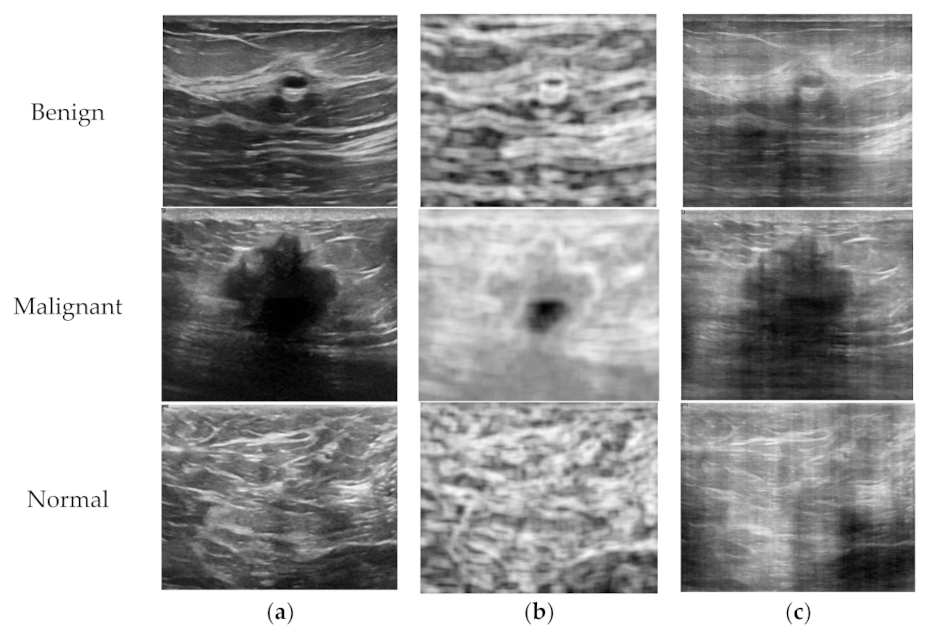

In this study, the entropy image was constructed from the B-mode image using a small moving rectangular window in both the axial and lateral directions. Although Wan et al. showed that the appropriate window length in the axial direction for a stable statistical parameter was three times the pulse length [25], the window used in this study was a fixed size of 25 × 25 pixels, which is the minimum size considering the average size of B-mode images, because detailed information on raw radiofrequency data was not available. The sample entropy images calculated from the B-mode image are shown in Figure 2b.

Figure 2.

Sample B-mode, entropy, and phase images for a patient in each class; (a) B-mode images, (b) entropy images, and (c) phase images.

In this study, we constructed a phase image from its B-mode image using its own phase information and the representative (or average) magnitude of the Fourier transform, which are averaged for the entire dataset. Because the image sizes of the dataset used in this study are different, the Fourier transform was performed with large enough data points first, and then the reconstructed image was re-sampled to its original size after the inverse Fourier transform with its own phase and the average magnitude components. The sample phase images calculated from the B-mode image are shown in Figure 2c.